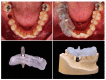

The purpose of this review is to examine various assessment methods in order to compare the accuracy between the virtually planned and clinically achieved implant positions. In this review, comparison methods using pre- and post-operative computed topography (CT) data and digital impressions for definitive prosthesis will be described. The method for the displacement and strain for quantification of the error will also be explored. The difference between the planned and the actual implant placement position in guided implant surgery is expressed as an error. Assessing the accuracy of implant-guided surgery can play an important role as positive feedback in order to reduce errors. All of the assessment methods have their own inevitable errors and require careful interpretation in evaluation.